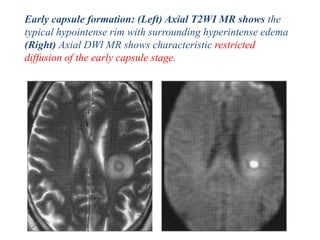

Early capsule formation: (Left) Axial T2WI MR shows the

typical hypointense rim with surrounding hyperintense edema

(Right) Axial DWl MR shows characteristic restricted

diffusion of the early capsule stage.